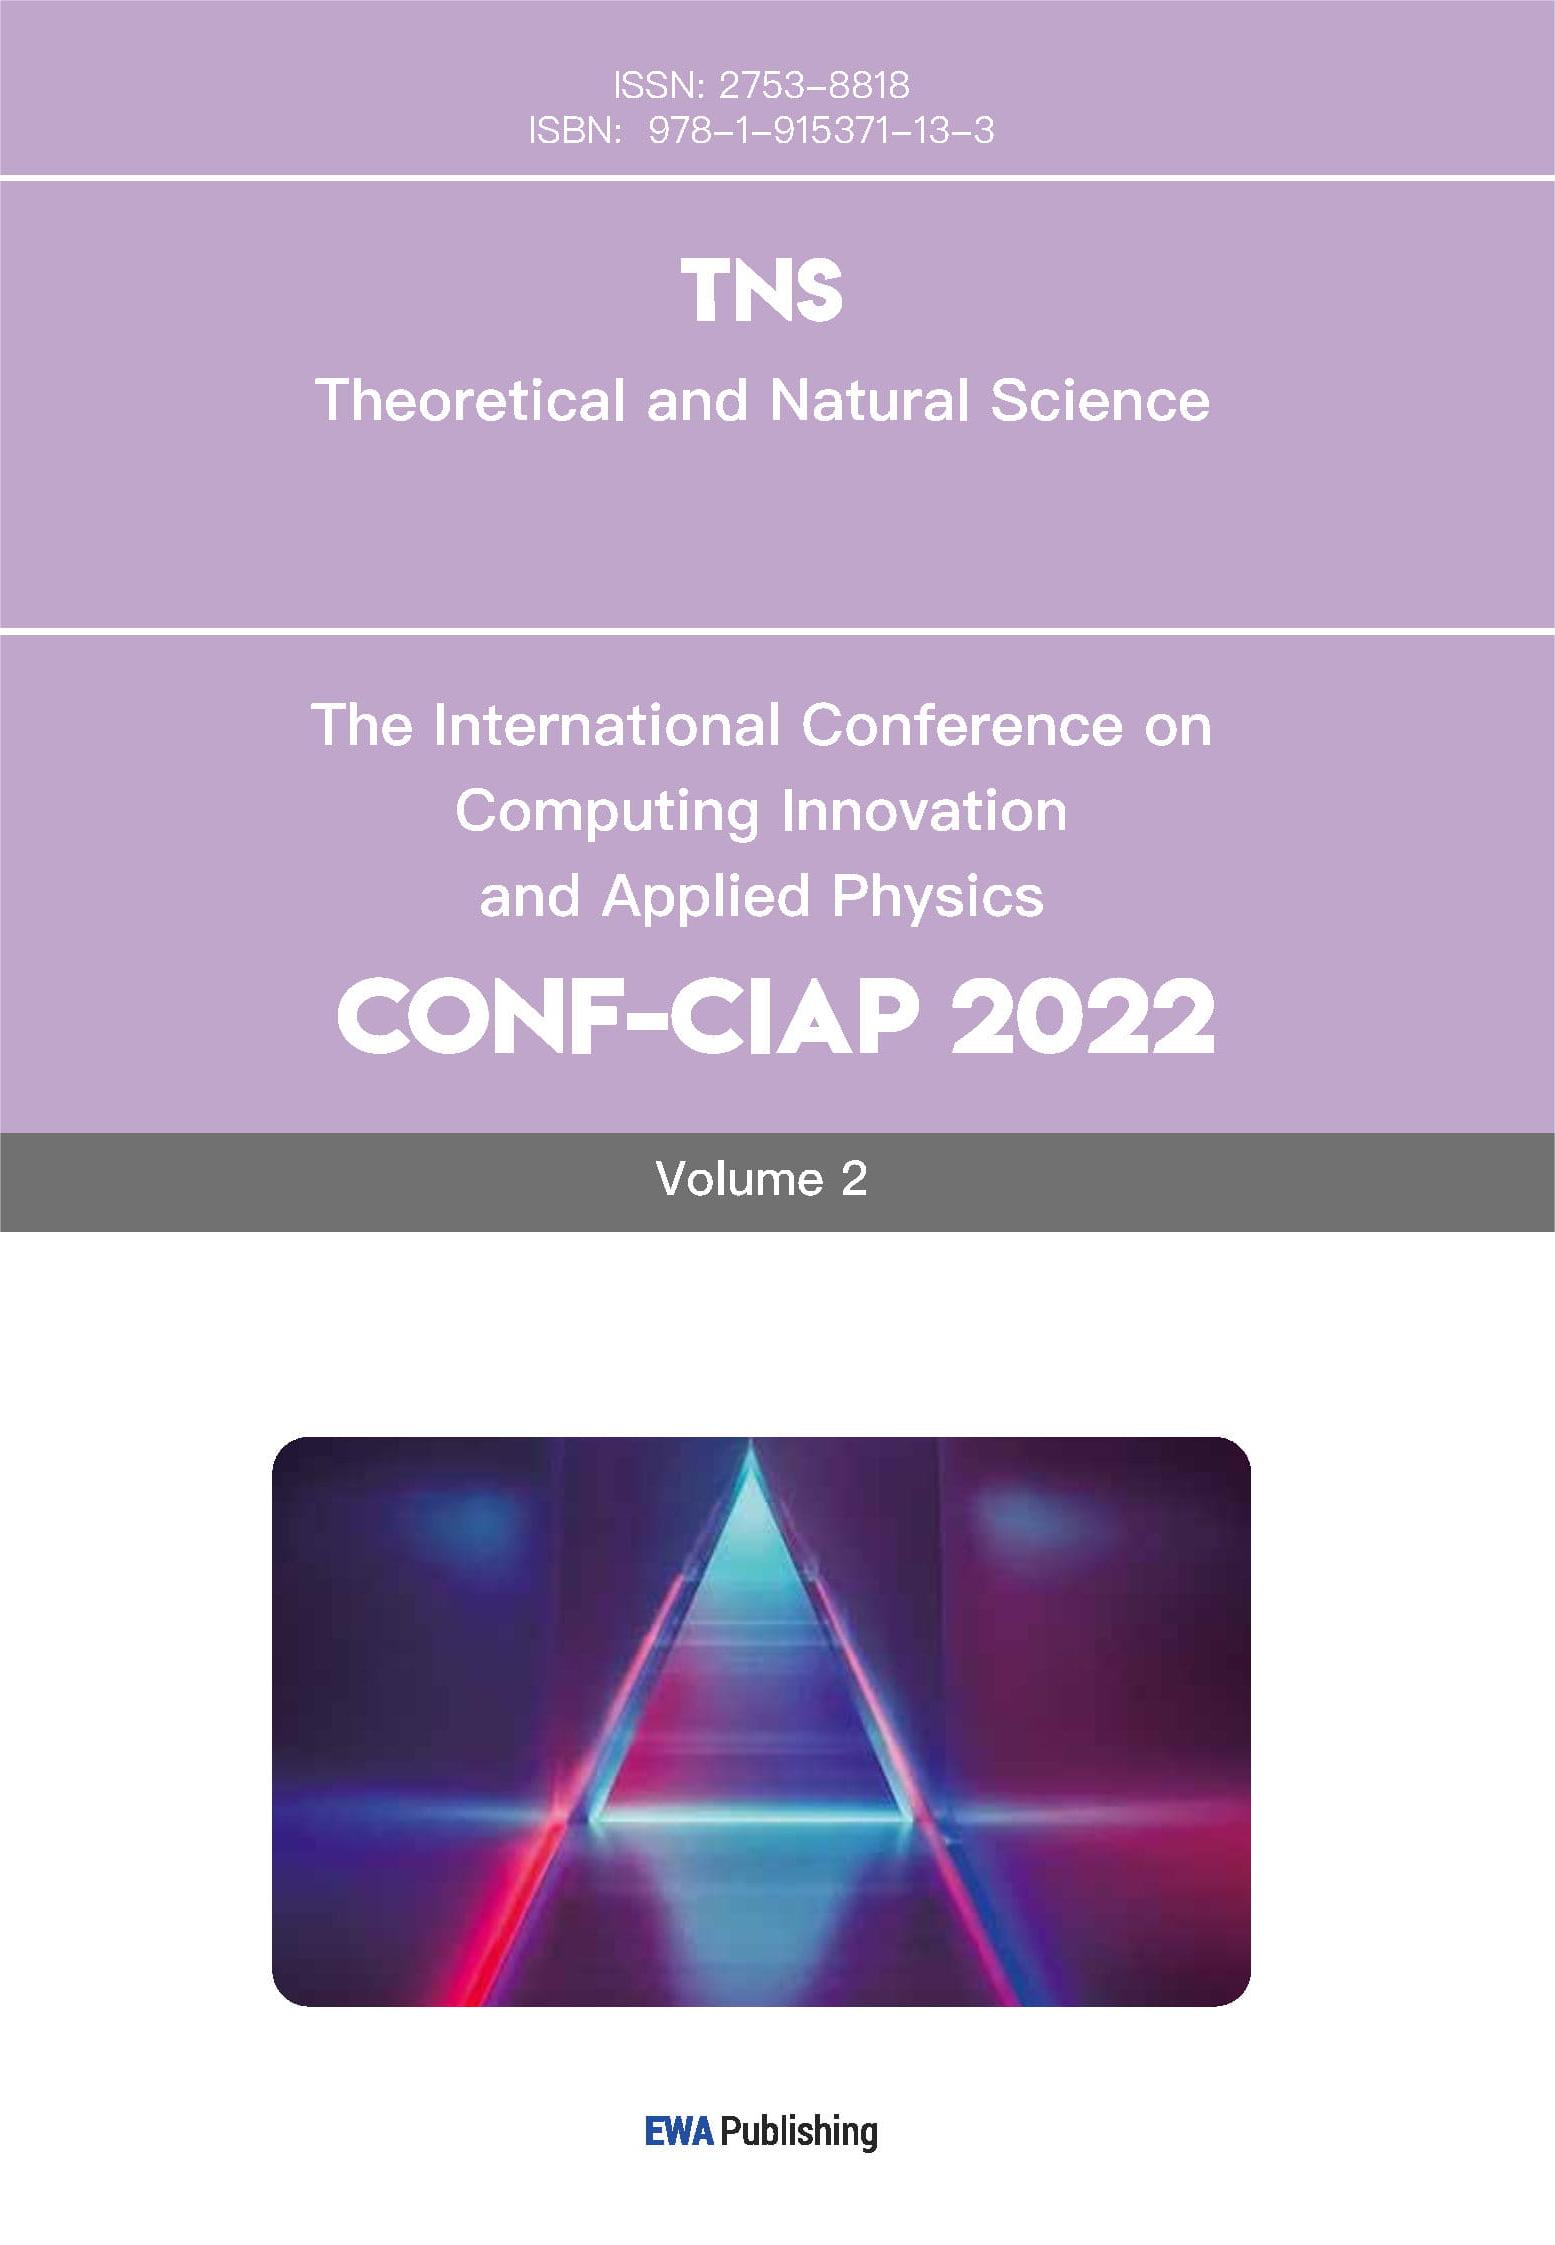

This research focused on finding DEGs between HCC and normal liver tissues. The TCGA dataset and the GSE45267 dataset from the NCBI were selected for analysis, both relevant to HCC. Bioinformatics and R-based analysis were employed to filter out the DEGs. From the TCGA dataset, 395 upregulated genes and 631 downregulated genes were identified (Figure 1A). Notably, genes such as BIRC5, CDC20, PTTG1, CCNB1, and UBE2C were upregulated in HCC, while CLEC4M, GDF2, FCN2, CRHBP, COLEC10, and FCN3 were downregulated (Figure 1B). Upregulated genes were primarily involved in pathways such as mitotic nuclear division, chromosome segregation, the cell cycle, nucleocytoplasmic transport, DNA replication, ribosome biogenesis, and spliceosome function. Conversely, the downregulated genes were found to be enriched in pathways associated with retinol metabolism, and chemical carcinogenesis, complement and coagulation cascades, drug metabolism, organic acid catabolism, xenobiotic metabolism, and fatty acid catabolism (Figure 1C).